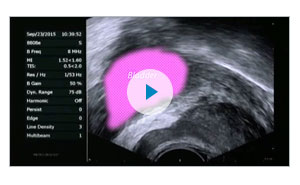

For Rezūm Therapy procedures, I practice the Modified Periprostatic Block, otherwise known as the “Beahrs’ block” (see video for more information). I’ve had tremendous experience with this, and my patients experience very minimal pain. I believe so much in the practice that I sought out a physician to perform the “Beahrs block” on me when I had Rezūm Therapy.